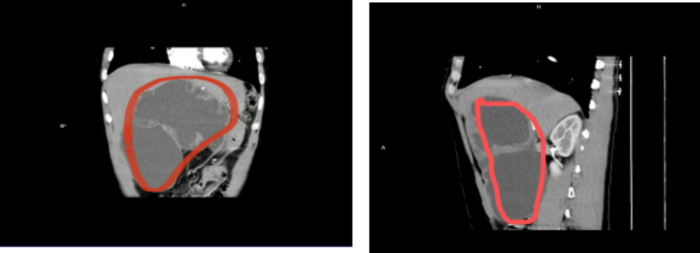

就在前不久,患者肚子突然剧烈地疼痛,便到毕节市第二人民医院普外科。通过腹部CT检查与临床经验的结合,最终诊断为“肝巨大占位性病变”,该肿物大小约173mm×78mm×184mm。

如此大的肿瘤,目前在毕节甚至在全国都非常少见,治疗的唯一手段就是切除,但要摘除在“生命禁区”里的如此巨大的肿瘤如同“排雷”,手术难度和手术风险极大。

12年的巨大肿瘤,4320天病痛的折磨,10万个小时的身心煎熬,经过5个小时的手术,肿瘤被成功摘除。